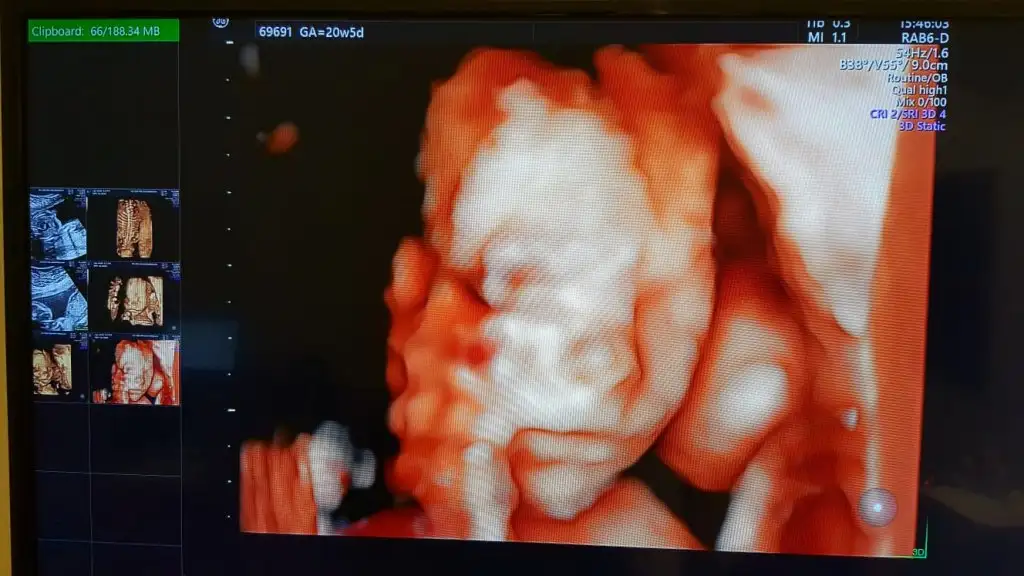

Nasil gecdi detayli ?Günaydın günaydınBugün ayrıntılı ultrasonumuz var güzel haberlerle dönmeyi ımut ediyorum dualarınızı esirgemeyin arkadaşlar.Doktora her gideceğimde geriliyorum nedense.

Evet canım hatırlıyorum güzeldi darısı başına arkadaşım şükür her şey yolunda dedi doktor bir saate yakın inceledi gerisi Takdir-i İlahiNasil gecdi detayli ?